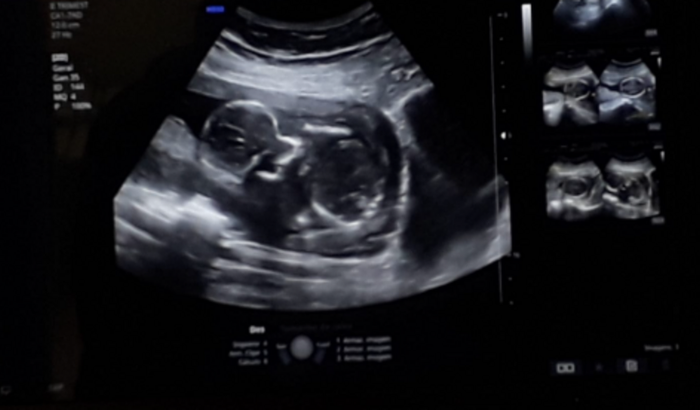

Olá, meu nome é Vanuza e sou moradora do município de Abelardo Luz, SC. Estou aqui para compartilhar a história da minha filha Celine, que está em uma luta pela vida desde antes de nascer.

Celine foi diagnosticada com trissomia 16, uma condição rara e grave que afeta os cromossomos de seu corpo. Isso significa que ela possui uma cópia extra do cromossomo 16, o que pode gerar diversas complicações para sua saúde. Além disso, ela enfrenta outros problemas de saúde, como:

A trissomia 16, por ser uma condição muito rara, traz uma chance de sobrevivência muito baixa. Apenas 1% dos bebês diagnosticados com essa condição sobrevivem após o nascimento. Porém, mesmo diante dessas dificuldades, queremos dar a nossa filha a oportunidade de lutar pela vida e oferecer a ela o maior cuidado possível. Os médicos nos deram 1% de chances de ela sobreviver, e vamos dar a ela a possibilidade da vida. Mesmo sendo atendidos pela saúde do município, não temos condições financeiras para arcar com as despesas que não são cobertas pelo SUS, tais quais, exames, medicamentos, aluguel de veículos para transporte adequado, já que os cuidados com qualquer tipo de solavanco, pode acorrer aborto espontâneo.